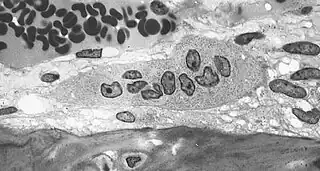

![]() Imagen tomada con un microscopio óptico en la que se observan osteoclastos positivos a la fosfatasa ácida tartrato resistente. | ||

Los osteoclastos se caracterizan por poseer una porción de su membrana "arrugada", en forma de cepillo, rodeada de un citoplasma libre de orgánulos llamada "zona clara", con la que se adhiere a la superficie del hueso mediante integrinas, unos receptores especializados del hueso. El proceso de resorción se inicia cuando el aparato de MRD de las células excreta lisosomas con enzimas capaces de producir un microambiente ácido por debajo de la membrana arrugada como consecuencia del transporte de protones mediante la bomba de protones ATP-dependiente, el intercambio Na+/H+ y la anhidrasa carbónica. Las enzimas lisosomales de los osteoclastos implicadas en este proceso son cistein-proteasas como la catepsina y sobre todo, la fosfatasa ácida tartrato-resistente (esta última se utiliza como marcador del fenotipo osteoclástico). Las enzimas lisosomales solo son liberadas en la zona clara en las proximidades del borde arrugado produciéndose en esta área las reacciones de degradación de la matriz que deben producirse antes de que el medio ácido disuelva las sales minerales del hueso.